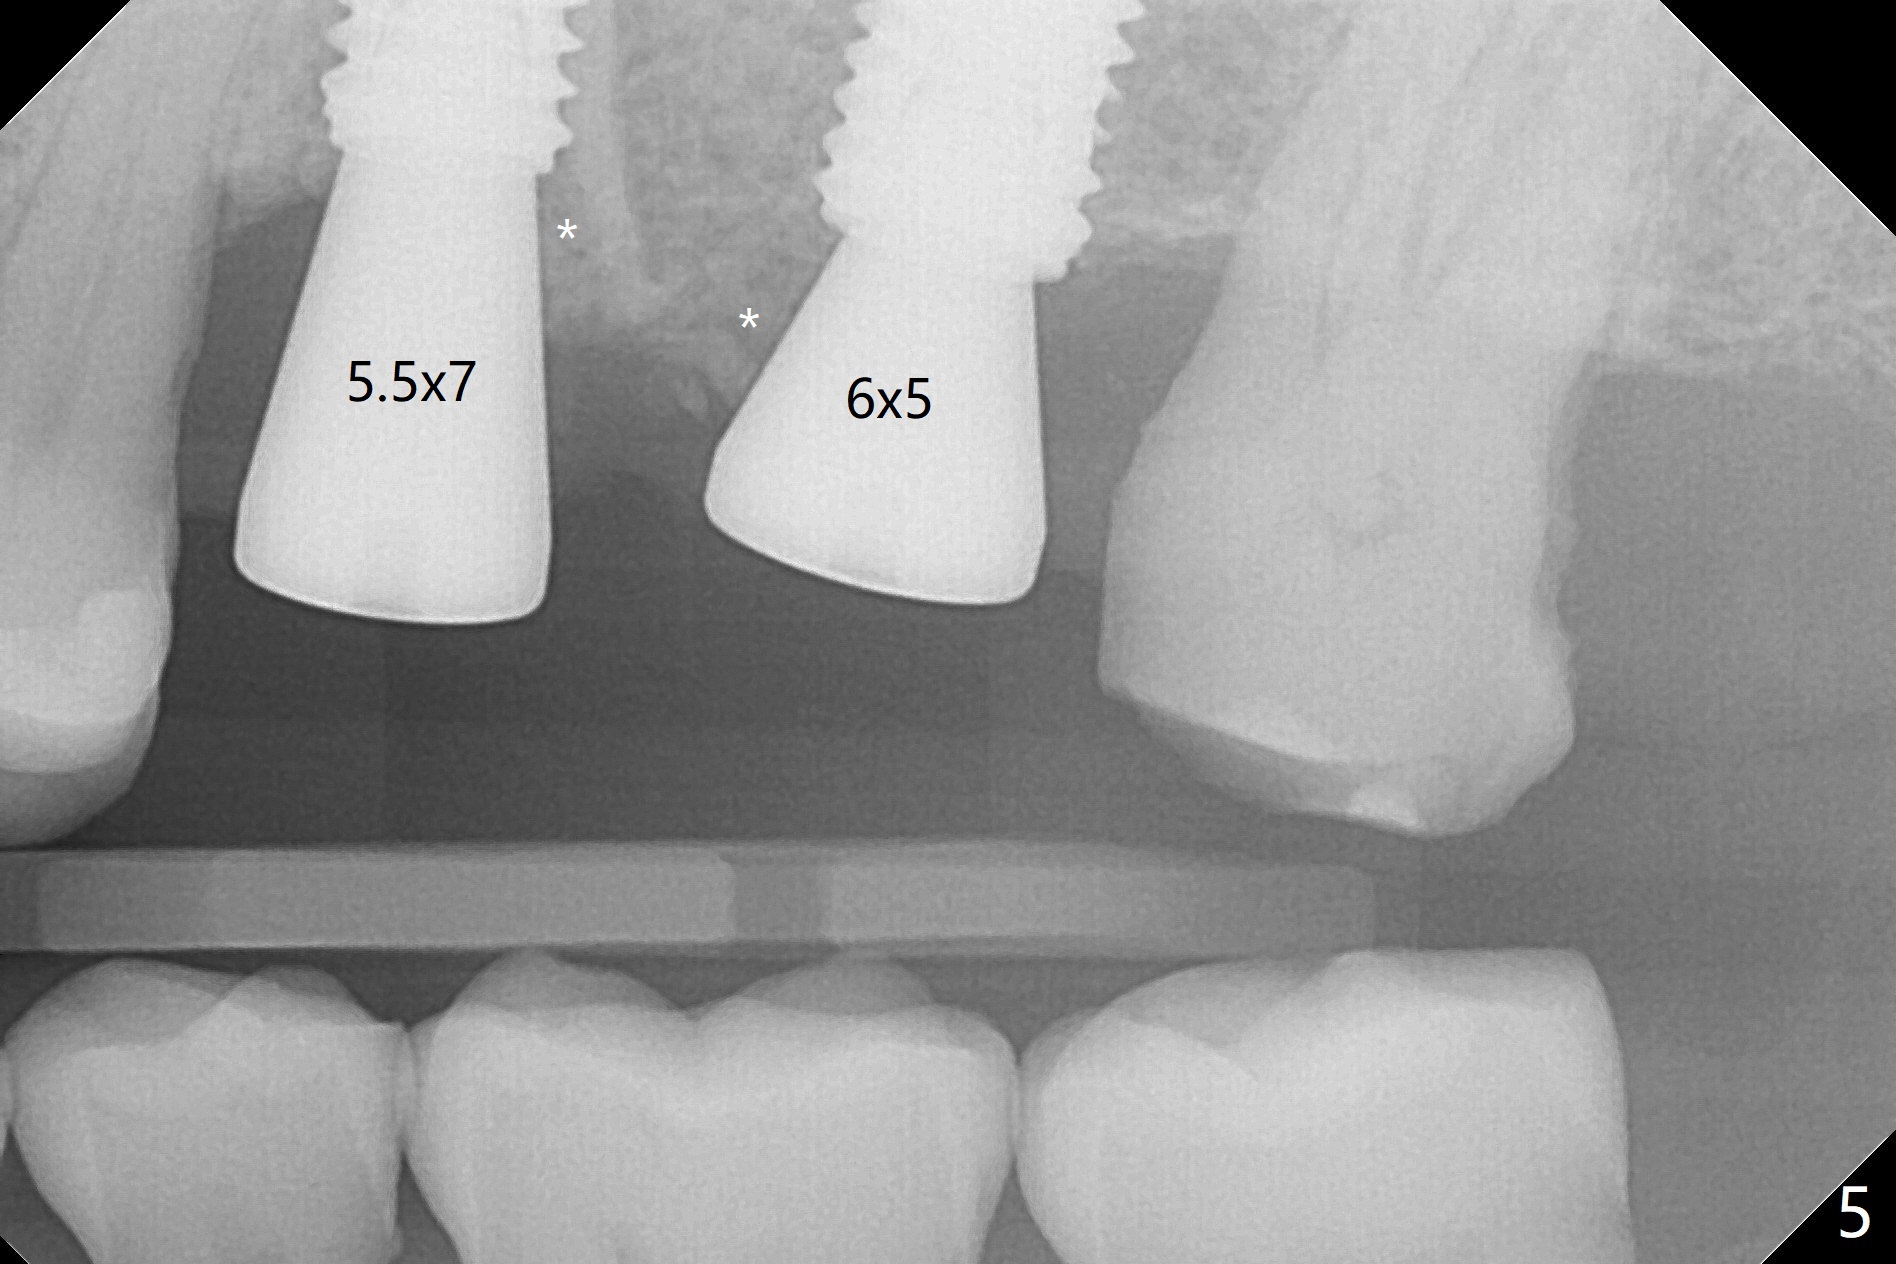

After extraction of the tooth #13 residual root, the bone in the distal wall of the socket looks white. Intraop PA rules out root structure (Fig.1 *). Osteotomy is conducted according to drill sequence. Bitewings are taken to check implant placement level (Fig.2,3). Following implant level adjustment and healing abutment installment (Fig.4,5 (*: bone graft)), the implant at #13 is found to be close the root of #12 (Fig.6 *), i.e., not parallel to the implant at #14. Introspectively, 2.2x10 mm drill seems to be long. When it touches the bone, the cylinder portion of the drill (Fig.7 red) does not engage into the sleeve (green). When it goes into the bone, it may have been deflected mesial due to the slope of the distal wall of the socket (hard bone, Fig.8 open arrow)). If a shorter drill (such as 2.2x7.3 or 8.5 mm) were used (Fig.9), the deflection would be minimal if drilling is slow (Fig.10). CT taken 1 week postop shows that the implant at #13 is approximately 1 mm near the root of the tooth #12, but the neurovascular bundle to the latter seems not to have been interrupted (Fig.11,12). The buccopalatal trajectory at #14 is within normal limit (Fig.11,13 (B: buccal)). There is no periapical radiolucency at #12 five months postop (Fig.14). However the cemented abutments are incompletely seated (<). The patient is reluctant to return for impression 17 months postop (due to coronavirus); with attention, the same abutment at #13 is reseated completely; an abutment with longer cuff and narrower diameter is also seated completely (Fig.15).